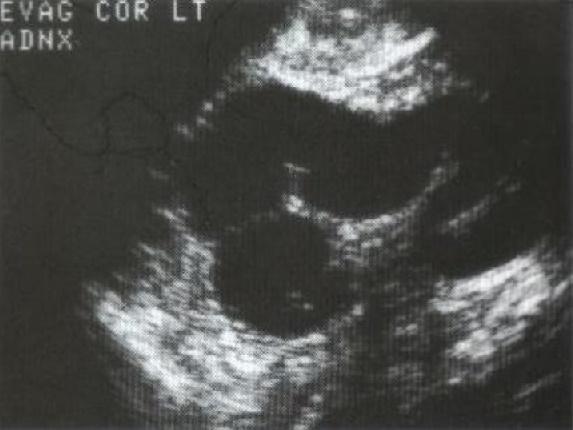

Absceso Tuboovárico (TOA)

Es una inflamación donde

la acumulación de material purulento se extiende más allá de los confines de las trompas.

Esta infección se ha dispersado a los ovarios y a la superficie peritoneal.

El TOA lo podemos observar unilateral o bilateral.

Es una lesión compleja que contiene fluido y material purulento, usualmente se observa la lesión en el CDS.

Hallazgos Sonográficos:

Usualmente observamos

una masa compleja con septaciones, márgenes irregulares y ecos internos; usualmente en el CDS.

Fluid- Fluid level

El ovario es difícil de reconocer o diferenciarlos de la masa.

Esta masa distorsiona la anatomía pélvica.